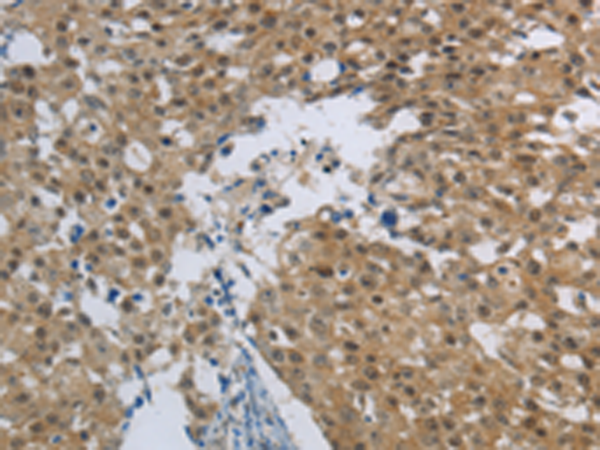

分类: 科研抗体货号: P11328别名: RPTPM, RPTPU, PTPRL1, hR-PTPu, R-PTP-MU应用: IHC反应种属: Human, Mouse